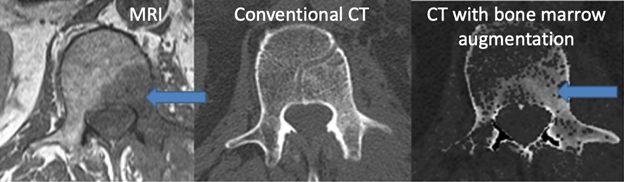

Enhanced CT visualization of pathology

PI: Joshua Polster, MD

Abstract:

We have developed post-processing techniques to enhance detection of bone marrow lesions and also soft tissue lesions using conventional single-energy CT data. For bone marrow lesion detection, a post-processing algorithm was created to enhance the soft tissue components of bone.  The technique has been preliminarily tested in clinical cases of MRI proven, CT-occult bone marrow lesions of the lumbar spine, demonstrating detection of lesions in 8 of 11 CT-occult lesions. For soft tissue lesion detection, a fluid-sensitive look-up table was created to mimic STIR MRI imaging with single-energy CT data.  A steak model has been evaluated with blinded independent reading from 4 musculoskeletal radiologists demonstrating the detectability of injected lesions in skeletal muscle, demonstrating excellent accuracy of lesion detection using this technique.